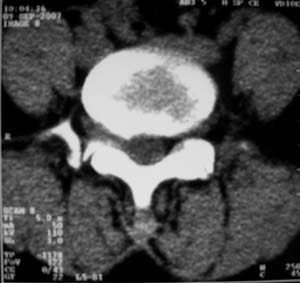

标题: CT9676:女,34岁,腰5骶1右侧神经根增粗?请各位老师会诊! [打印本页]

标题: CT9676:女,34岁,腰5骶1右侧神经根增粗?请各位老师会诊!

女,34岁,腰背部及右下肢酸痛两年余.

神经源性肿瘤可能性大;1椎间孔较对侧明显大,2相应层面似见椎间盘边缘.建议作mri.

神经源性肿瘤?突出?椎间盘扫描的层厚太厚了。建议mri或薄层扫描

对比观察

[emb10]为什么说是椎间盘病变呢?还有椎间盘脱出有脱向头端方向的吗?

腰间盘突出是有的,右侧椎间孔增大,还是做个mri吧。

右侧椎间孔显宽,考虑为体位不对称所致.扫描层厚偏厚了,考虑孔间型间盘突出.